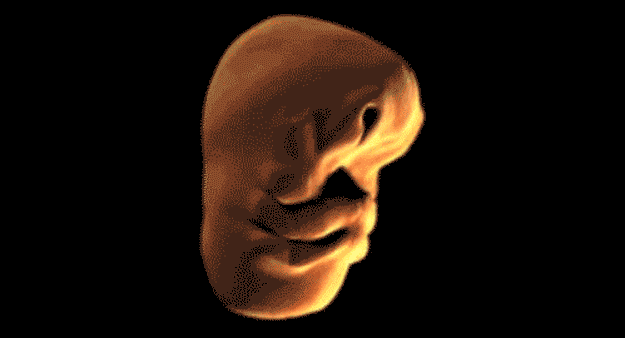

4. Sıradaki gif, insan yüzünün ana rahmindeki gelişimini anlatıyor: